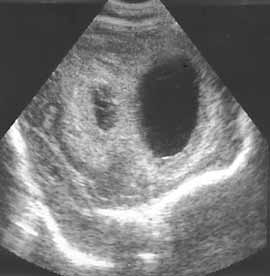

Рис. 2. Клебсиелезный менингит. Вентрикулит.

Ультразвуковая диагностика гнойных менингитов у детей первого года жизни.